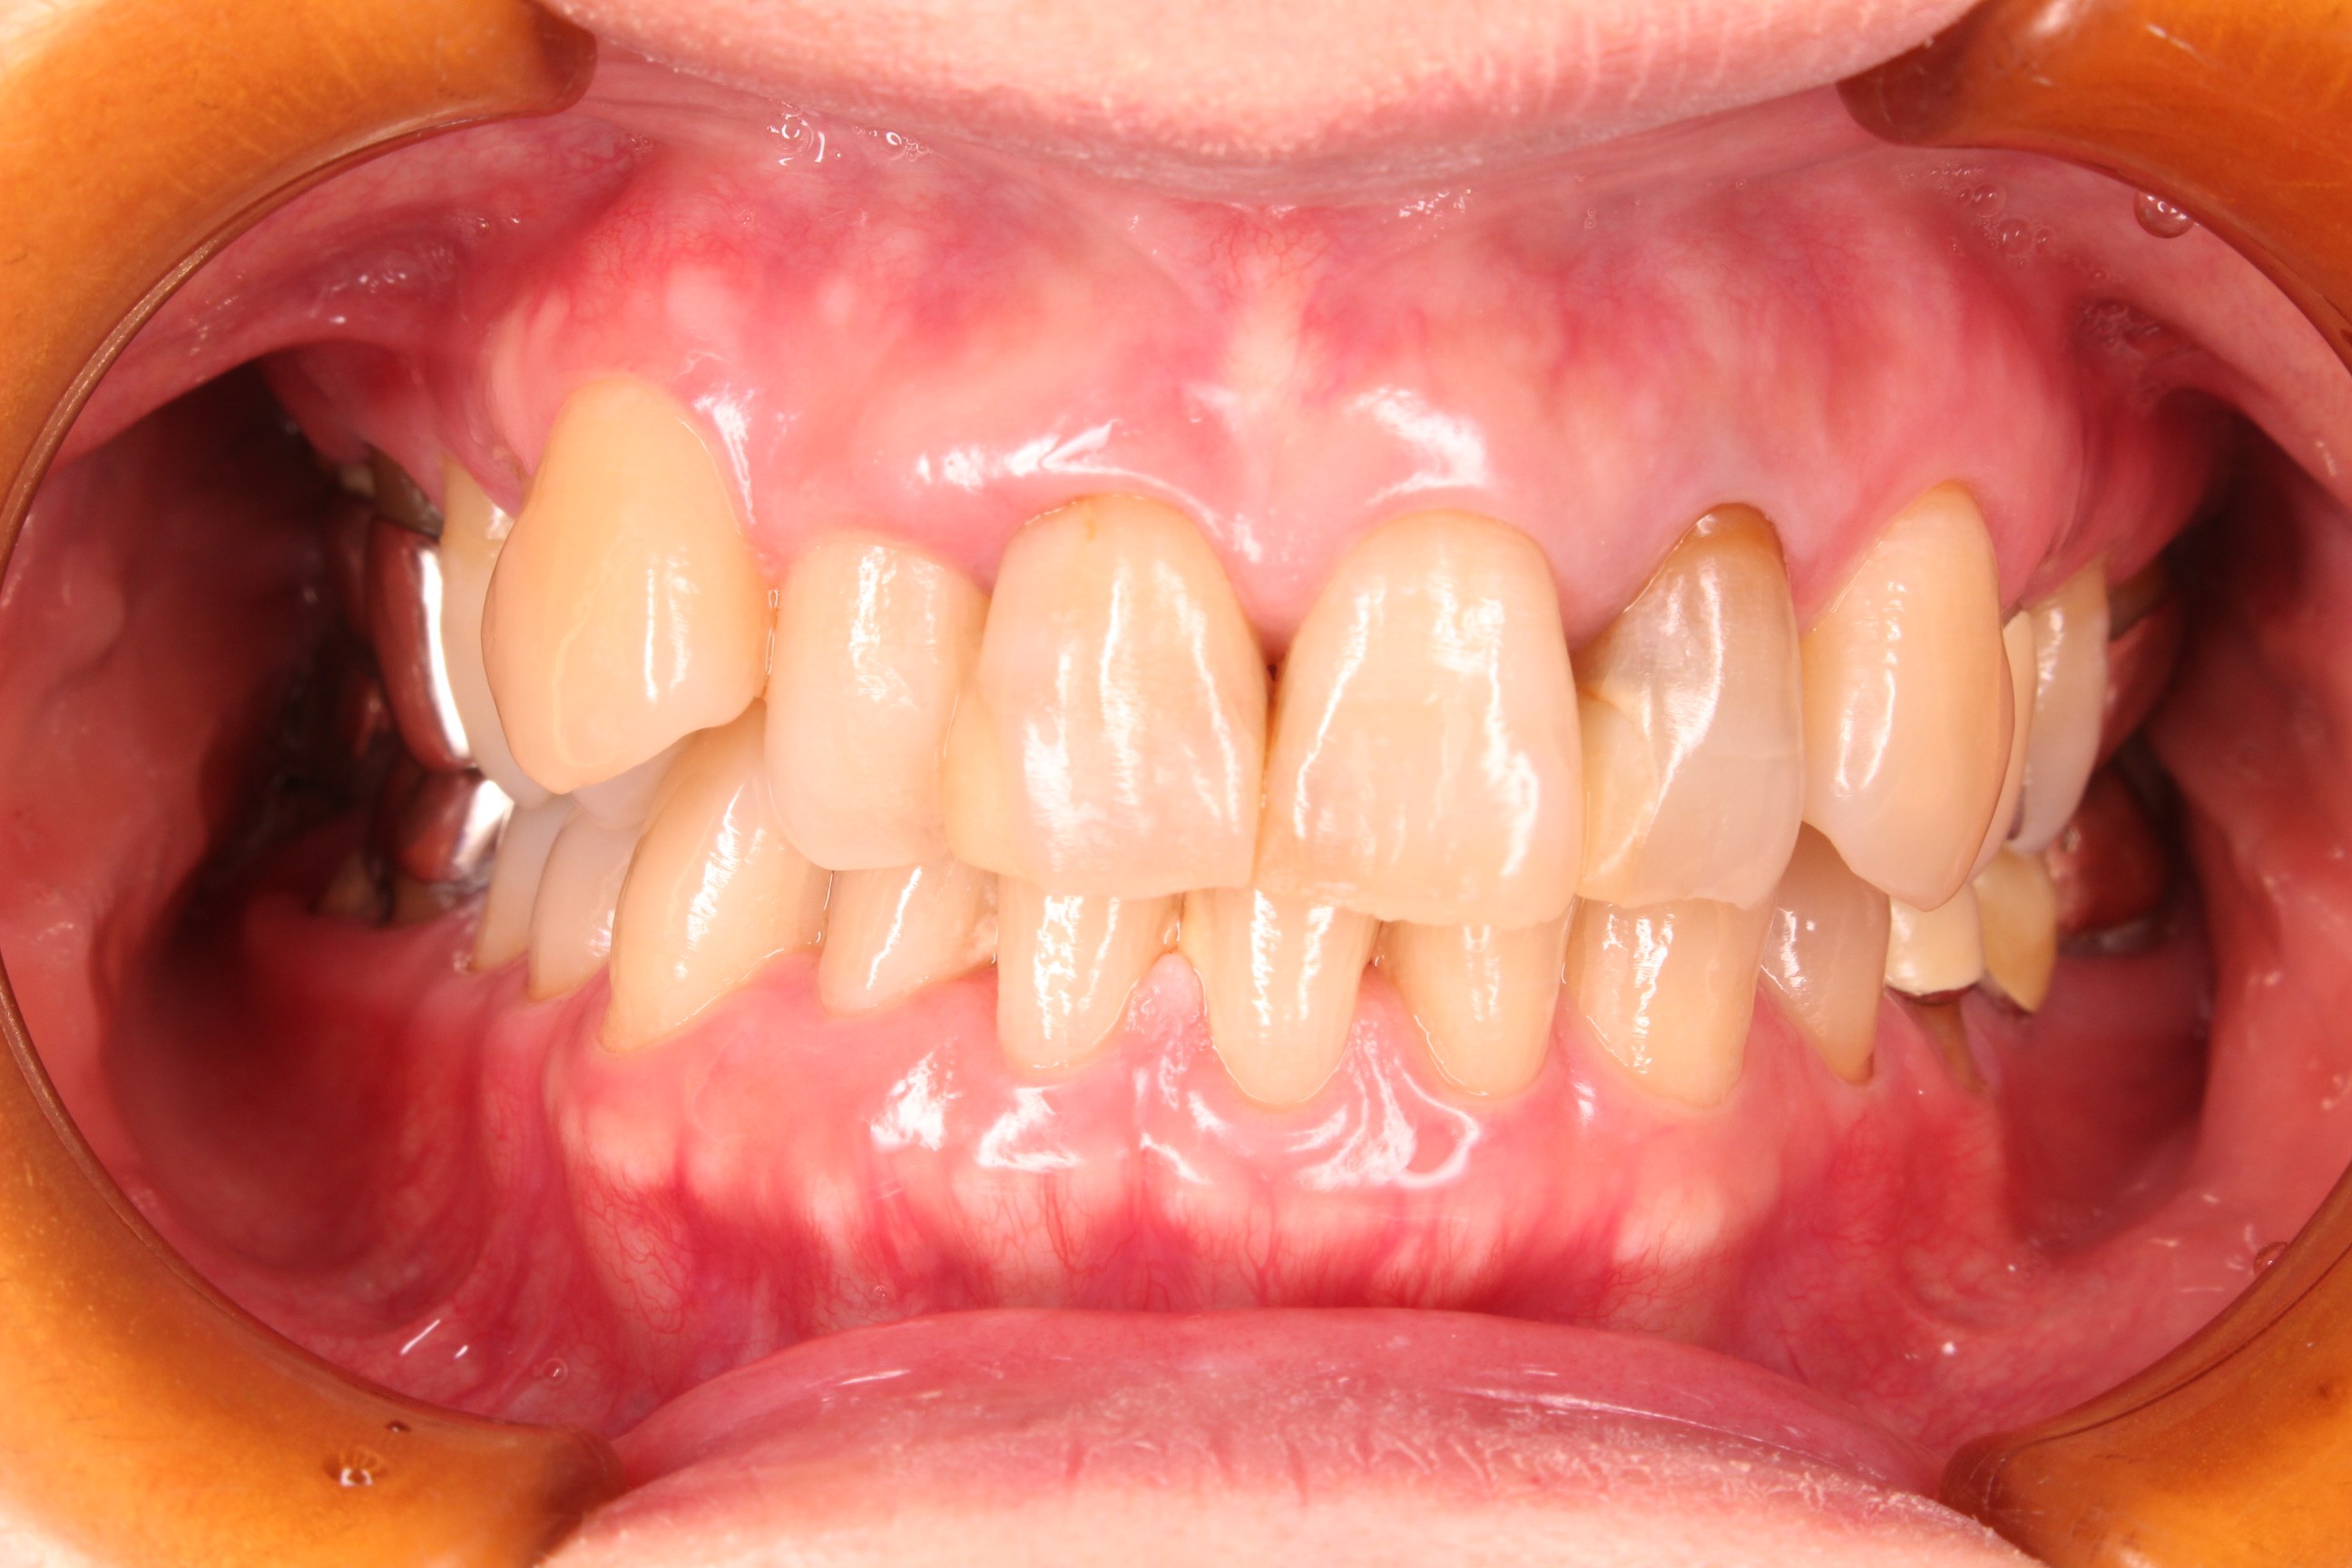

(治療後)

お手入れと治療の両立が行えて初めて歯周病は改善します。

残念ながら、既に歯周病により歯を支える骨が溶けている場合、炎症が引いた歯茎は、吸収した今の骨のラインまで後退しますが、お互いに一生懸命努力した結果、とても綺麗な口腔内に戻る事ができました。

歯周病治療は、綺麗で清潔な状態を長く保つ事が大切です。